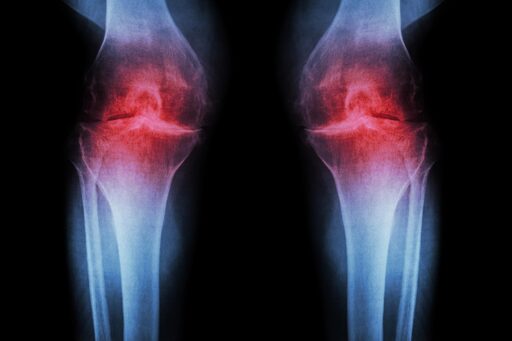

Researchers at Stanford Medicine report that blocking a protein linked to aging can restore cartilage that naturally wears away in the knees of older mice. In the study, the injectable treatment not only rebuilt cartilage but also stopped arthritis from developing after knee injuries similar to ACL tears, which are common among athletes and active adults. A pill-based version of the same therapy is already being tested in clinical trials aimed at treating muscle weakness associated with aging.

Human knee tissue collected during joint replacement surgeries also responded positively to the treatment. These samples, which include both the joint’s supporting extracellular scaffolding, or matrix, and cartilage-producing chondrocyte cells, began forming new cartilage that functioned normally.

Together, these findings point to the possibility that cartilage lost through aging or arthritis could one day be restored using a localized injection or an oral medication, potentially eliminating the need for knee or hip replacement surgery.